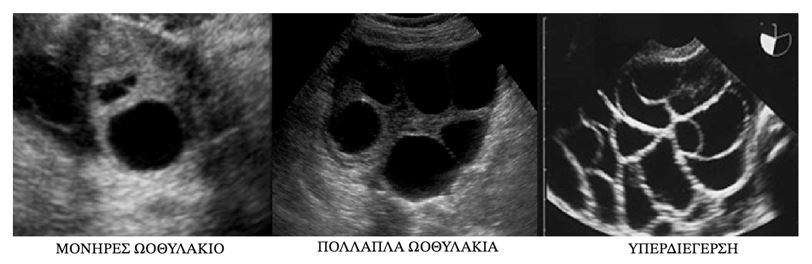

1. ΔΙΕΓΕΡΣΗ ΩΟΘΗΚΩΝ

Με ειδικά ορμονικά σκευάσματα που προσομοιάζουν των ανθρώπινων ορμονών επιχειρείται η πρόκληση της παραγωγής πολλαπλών ωαρίων σε αντίθεση με το ένα και μόνο ωάριο που απελευθερώνεται σε κάθε κύκλο, γιατί κατά τη διαδικασία αυτή δεν γονιμοποιούνται όλα τα ωάρια που παράγονται από τις ωοθήκες, ούτε και όλα αναπτύσσονται ομαλά μετά την γονιμοποίησή τους. Κατά τη διάρκεια της χορήγησης των φαρμάκων αυτών που είναι κυρίως ενέσιμα, πλην της κιτρικής κλομιφαίνης και της λετροζόλης που λαμβάνονται από το στόμα, παρακολουθείται η πορεία της διέγερσης και η ανταπόκριση στα φάρμακα συνήθως μέρα παρά μέρα, με υπερηχογράφημα και μέτρηση της οιστραδιόλης.

Συνήθως χρειάζονται 8-14 ημέρες διέγερσης πριν την χορήγηση hCG που προάγει το τελικό στάδιο ωρίμανσης των ωαρίων, 34-36 ώρες πριν την ωοληψία. Το 20% των κύκλων διακόπτονται πρόωρα, όπως συχνότερα συμβαίνει σε γυναίκες μεγαλύτερες των 35 ετών, για διάφορους λόγους είτε γιατί είναι φτωχή η διαφαινόμενη συγκομιδή των ωαρίων, είτε γιατί είναι παράδοξη η ανταπόκριση της ωοθήκης στην αγωγή με το σχηματισμό κύστης, είτε γιατί προβάλει έντονα ο κίνδυνος υπερδιέγερσης της ωοθήκης. H επιλογή των φαρμάκων και του σχήματος με το οποίο χορηγούνται σε χρονική σχέση με τον κύκλο εξατομικεύεται ανάλογα με την ηλικία και το όποιο ιστορικό προηγούμενων προσπαθειών.